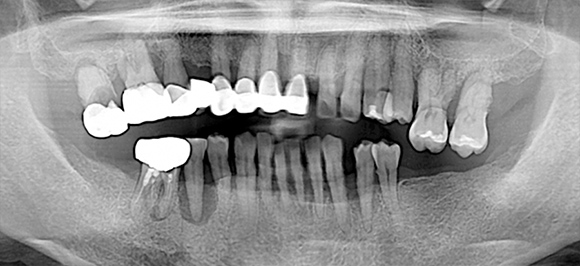

임플란트 틀니

임플란트의 장점인 튼튼한 고정력과 유지력을

잇몸 전체를 덮는 틀니와 결합하여

단일 틀니 사용으로 생길 수 있는 불편함을 개선